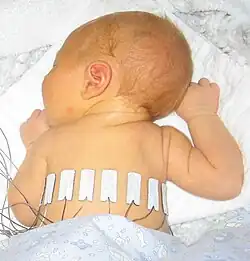

The above image shows an EIT study of a 10-day-old baby breathing normally with 16 adhesive electrodes applied to the chest.

After many years of lung EIT research with provisional EIT equipment or series models manufactured in very small numbers, three commercial systems for lung EIT have entered in the medical technology market: Timpel Medical - ENLIGHT 2100, Dräger's PulmoVista® 500 and Sentec's LuMon EIT. The models are currently being installed in intensive care units and are already used as aides in decision-making processes related to the treatment of patients with acute respiratory distress syndrome (ARDS).

- ^ a b S. Heinrich, H. Schiffmann, A. Frerichs, A. Klockgether-Radke, I. Frerichs, Body and head position effects on regional lung ventilation in infants: an electrical impedance tomography study. Intensive Care Med., 32:1392–1398, 2006.

- ^ S. Heinrich, H. Schiffmann, A. Frerichs, A. Klockgether-Radke, I. Frerichs, EIDORS contributed data [1] 2011